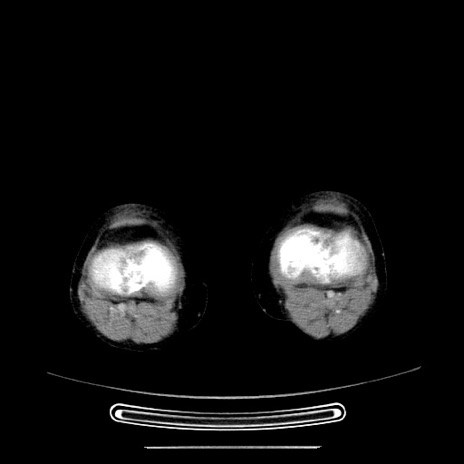

症例5(横断像)

【症例】70歳代女性

【主訴】お腹が張る

【現病歴】1週間くらい前から腹部膨満の自覚あり。昨日夜から増悪したため、本日救急外来受診。

【身体所見】意識清明、BT 36.5℃、BP 165/106mmHg、HR 80bpm、SpO2 98%、腹部:膨満、軟、自発痛・圧痛なし、触診にて不快感あり、腸蠕動音:減弱

【データ】WBC 12600、CRP 1.04